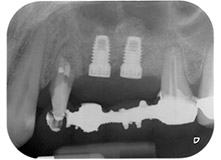

Une patiente de 58 ans se plaignait de douleurs et d'une mobilité accrue de la dent pilier 24 de son bridge. Présence d'une inflammation parodontale avec formation de poches de 7 mm de profondeur dans le sens mésiobuccal et de plus de 12 mm dans le sens distal, ainsi que d'une atteinte de la furcation au troisième degré. La radiographie a par ailleurs révélé une lésion parodontale étendue autour de la région apicale de la dent 24 ayant préalablement reçu un traitement endodontique (alio loco) (Fig. 1).

Un an plus tôt, les dents 25 et 26 avaient été extraites à la suite d'un traumatisme et pour cause d'atteinte endo-parodontale, avant la pose du bridge. Une lésion endo-parodontale combinée a été diagnostiquée pour la dent 24, d'étiologie incertaine. La patiente voulait conserver ses dents piliers 24 et 27 et refusait toute prothèse amovible à titre définitif, et même provisoire. Par conséquent, malgré un pronostic défavorable compte tenu des résultats des radios et des examens cliniques, il a été convenu de faire le maximum pour conserver les deux dents.